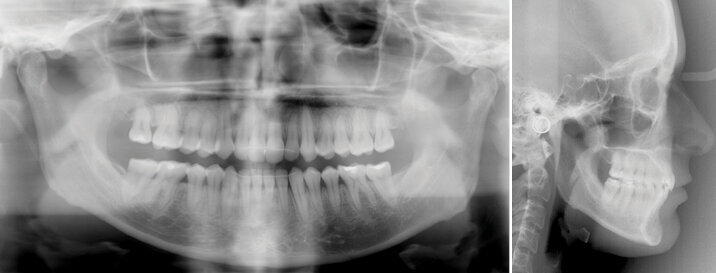

Vstupní foto a RTG dokumentace